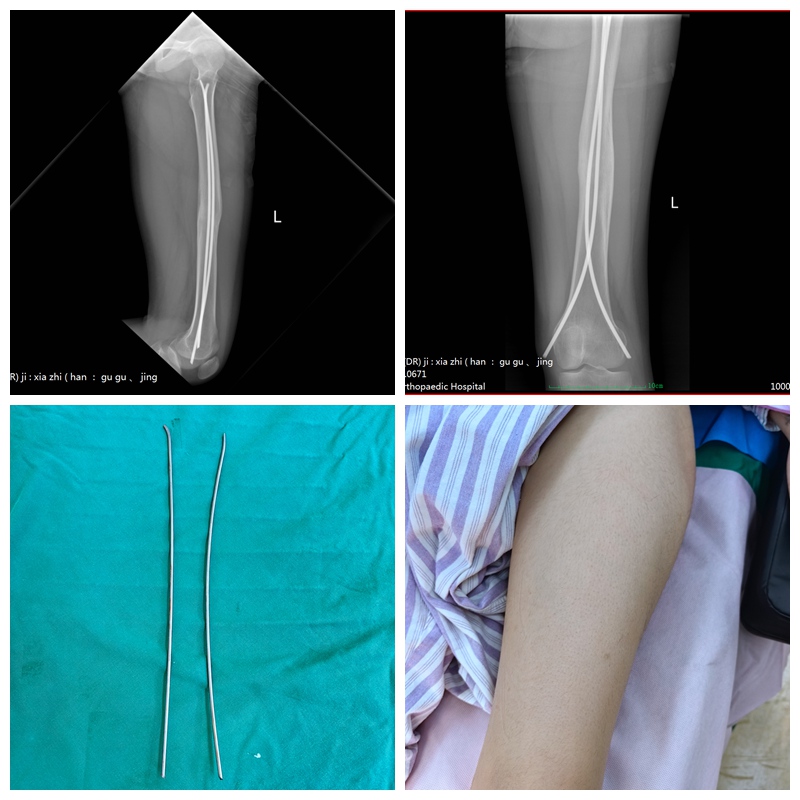

胫骨骨折案例

13岁的王同学,因左胫骨骨折术后9月余前来取钉。影像复查显示骨折愈合良好。由创伤与手足显微外科丁治红主任主刀,顺利为其施行了“左胫骨骨折术后内固定取出术”。由于初次手术即为微创操作,此次取出术后疤痕极小,出血少,恢复快,最大程度满足了青少年对功能与美观的双重需求。